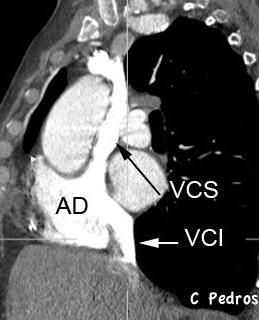

“De abertura torácica a diafragma”.

Contiene: Grasa. Aorta y ramas

Venas ácigos y hemiácigos

Troncos simpáticos y nervios esplácnicos

Aneurisma aórtico

Ganglios, conducto torácico y cisterna chili.

Plexo venoso lumbar

Restrepo CS et al.. The diaphragmatic crura and retrocrural space: normal imaging appearance, variants, and pathologic conditions . Radiographics. 2008